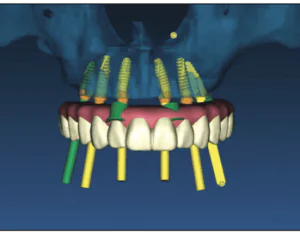

INTRODUCTION Reconstruction of edentulous areas with dental implants is a viable alternative to conventional dental procedures and has become rather mainstream within the profession and